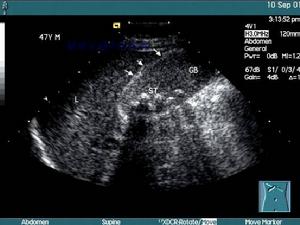

根據典型病史,突發性右上腹絞痛,陣發性加重,右上腹膽囊區壓痛、肌緊張,體溫升高,即可診斷。超聲見膽囊腫大壁厚收縮不良或合併膽石等診斷就更明確。如觸到張力很大的膽囊或體溫在39~40℃病情不緩解等應考慮膽囊壞死、穿孔的危險增大,有可能引起腹膜炎。